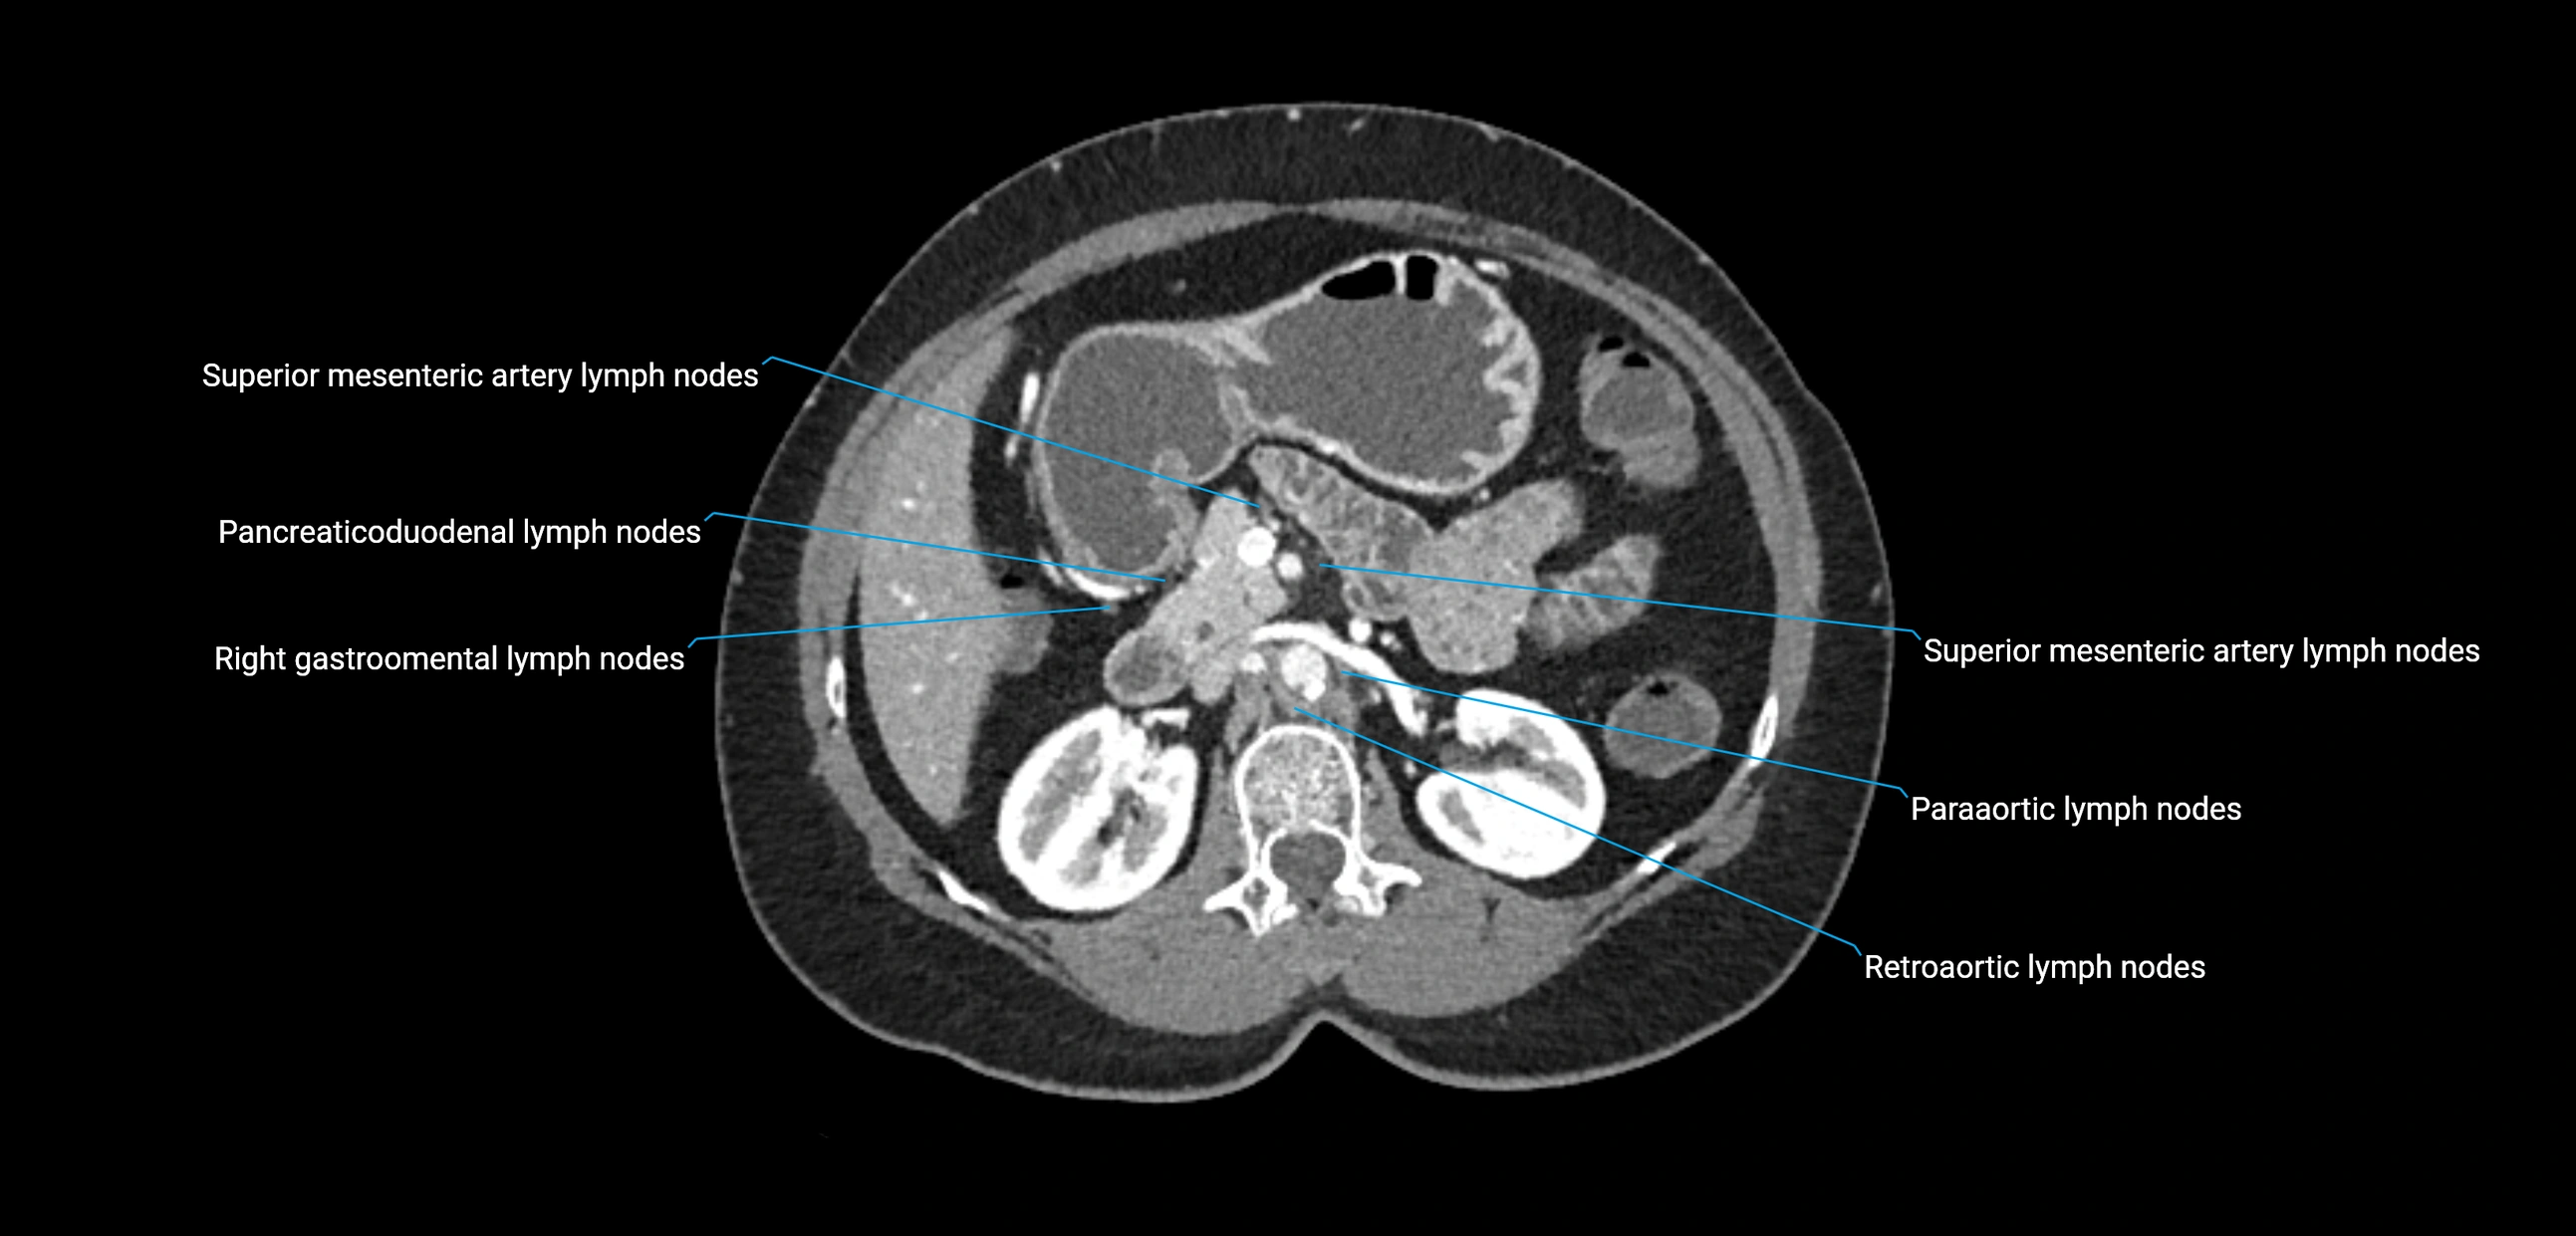

CT Appearance

CT Pre-Contrast:

• Nodes appear as soft-tissue density nodules adjacent to the aorta and IVC

• Calcification may be seen in chronic infections (e.g., tuberculosis)

CT Post-Contrast:

• Normal nodes enhance homogeneously

• Malignant nodes may show heterogeneous enhancement, central necrosis, or conglomerate formation

• Size >1 cm short axis is suspicious, though morphology and distribution are equally important

CT Venography (CTV):

• Demonstrates nodal encasement or compression of adjacent vessels (aorta, IVC, renal veins)

• Useful in staging testicular and ovarian malignancies

• Provides 3D reconstructions for retroperitoneal lymph node dissection planning